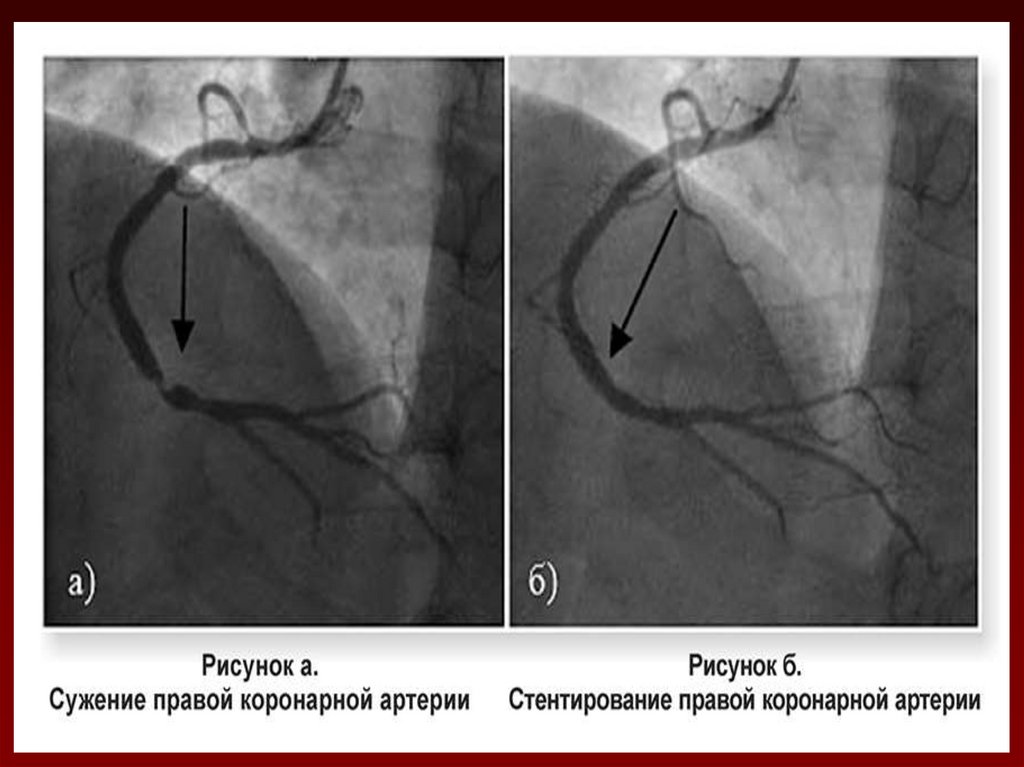

45. КОРОНАРОГРАФИЯ

• Дает информацию о

наличии стенозирующих

изменений коронарных

артерий и их тяжести.

• Пациенты с

многососудистым

поражением и со

стенозом ствола левой

коронарной артерии

имеют более высокий

риск серьезных

осложнений

заболевания.